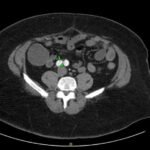

Acute aortic dissection is a life-threatening event caused by separation of the aortic layers that requires prompt management and surgical consultation. We present the case of a 53-year-old male who developed acute, severe chest pain radiating to his back at a community hospital and was transferred to a tertiary center for definitive surgical management. The patient’s aortic dissection was diagnosed via computed tomography angiography. He was started on rate-control and blood pressure medications, and was admitted emergently to the operating room. Emergency physicians should obtain immediate surgical consultation, promptly start medications for rate and blood pressure control, and administer analgesia in order to stabilize their patient and decrease the shear forces that would further propagate an aortic dissection.